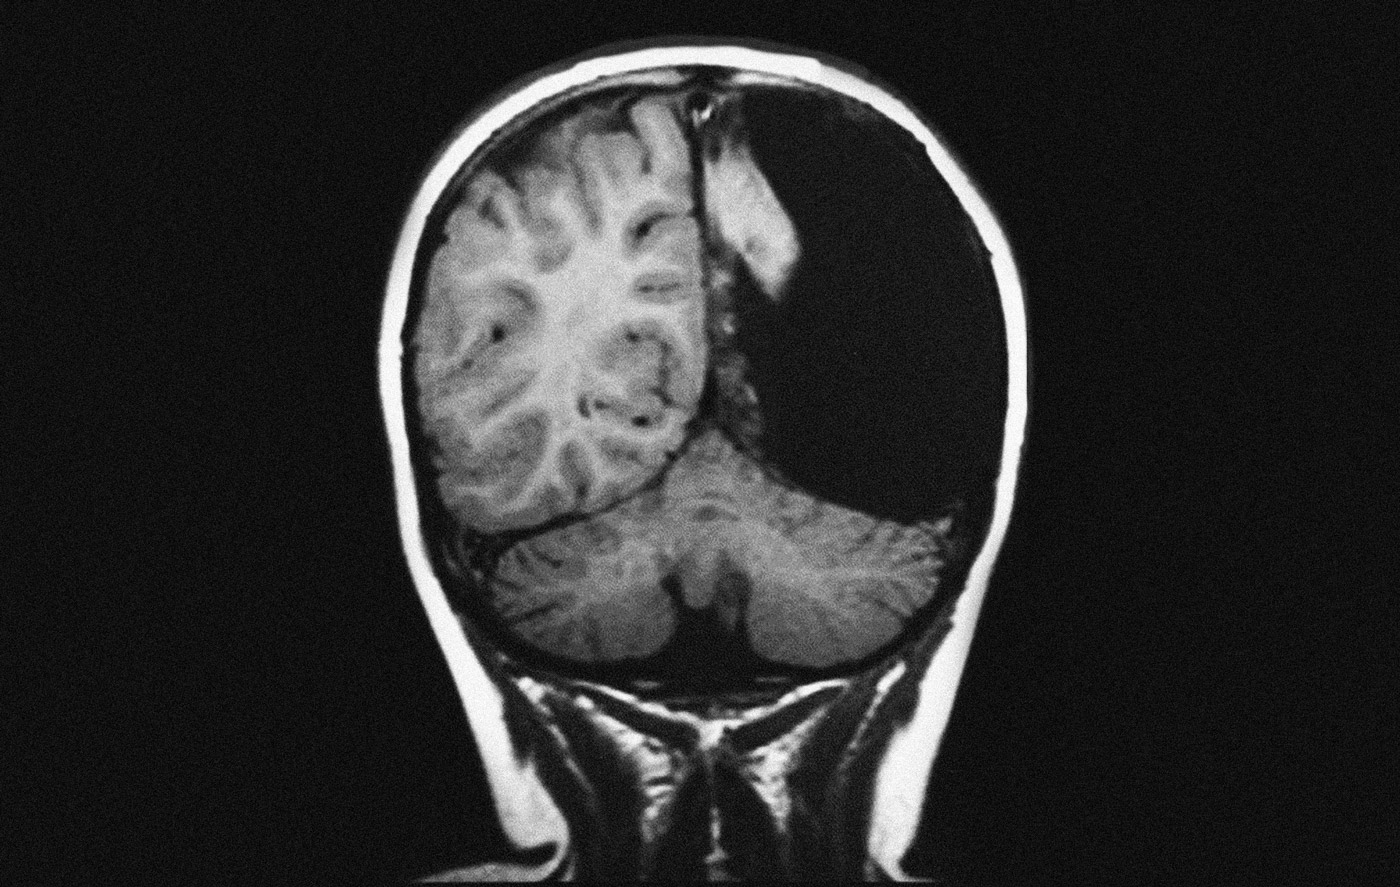

Необычные находки: инородные тела на рентгенограмме брюшной полости